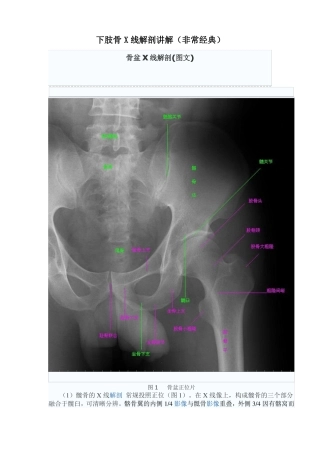

下肢骨 X 线解剖讲解(非常经典)骨盆 X 线解剖(图文)图 1骨盆正位片(1)髋骨的 X 线解剖 常规投照正位(图 1)。在 X 线像上...